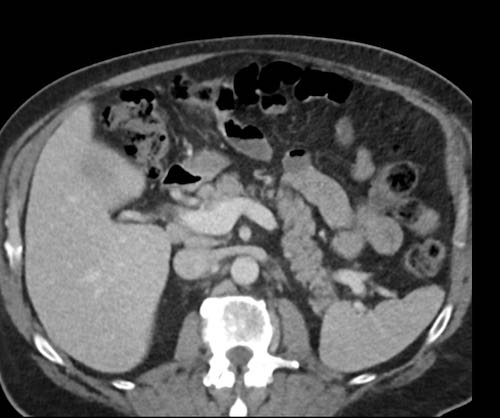

Ca lâm sàng 2

Cuộn qua các lát cắt.

Bạn có thể phát hiện tất cả các tổn thương cấy ghép phúc mạc không?

.jpeg)